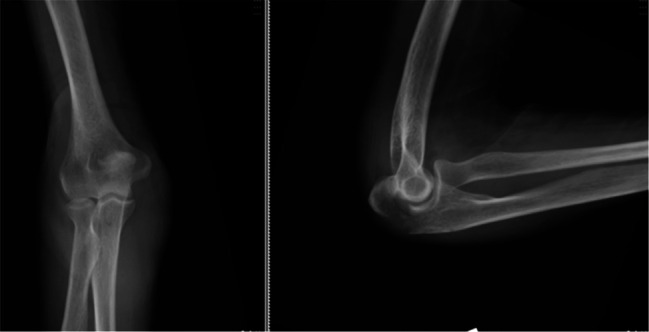

Abstract Image